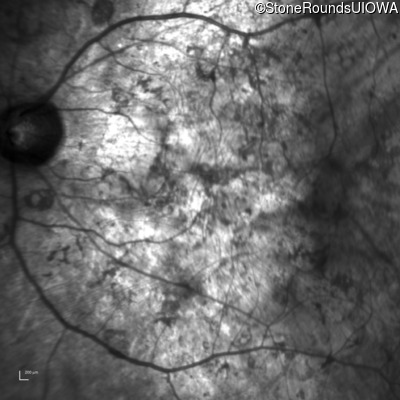

Infrared Fundus Photograph - Left - Hand Motion

Exemplar